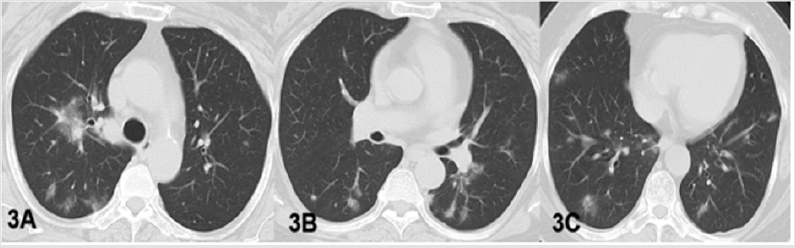

b. Case 2 Woman 56Y, with fever and dry cough for 1 day. The husband had contact with people from wuhan. She underwent three plain chest CT scans (Figure 3), with slight absorption of pulmonary lesions. Both swabs and deep sputum samples and blood samples were negative for the new coronavirus nucleic acid. The patients were still hospitalized for observation.

Figure 3: CT findings of case 2 in isolation group. 56-year old woman whose husband had contact with a Wuhan resident. Her CT scan showed normal at the beginning of the disease (2020/1/25). (A-C): 7 days later, chest CT images of this patient displayed multiple patchy and nodular ground glass shadows in both lungs (2020/2/1).